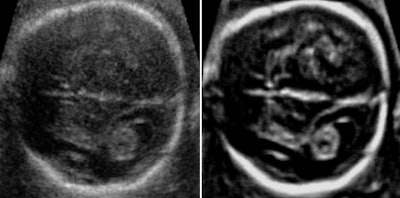

Fetal spine evaluated using skeletal view rendering with a sepia color map (left) and standard color map (right).In fetal brain examinations, 3D imaging provides a full volume of the fetal brain. Adaptive volume enhancement and true-to-data rendering -- which combines adaptive volume enhancement, scan conversion, and rendering to yield high resolution and fewer image approximations -- can also improve clinical value and make it easier to perform the study. 3D ultrasound fetal brain measurements are more accurate and reproducible than their 2D counterparts, according to Selbing.

Fetal brain on an A-plane image before volume enhancement (left) and after adaptive volume enhancement was applied to the raw image volume (right).Furthermore, in fetal cardiology, 4D technology with color Doppler and a transparent image view can provide an improved view of the spatial relationship of the cardiac anatomy, specifically the relationship between both ventricles, the greater vessels, and the cardiac chambers, said Dr. Marius Vicea Calomfirescu of Bucharest, Romania, in a talk at ISUOG 2015.